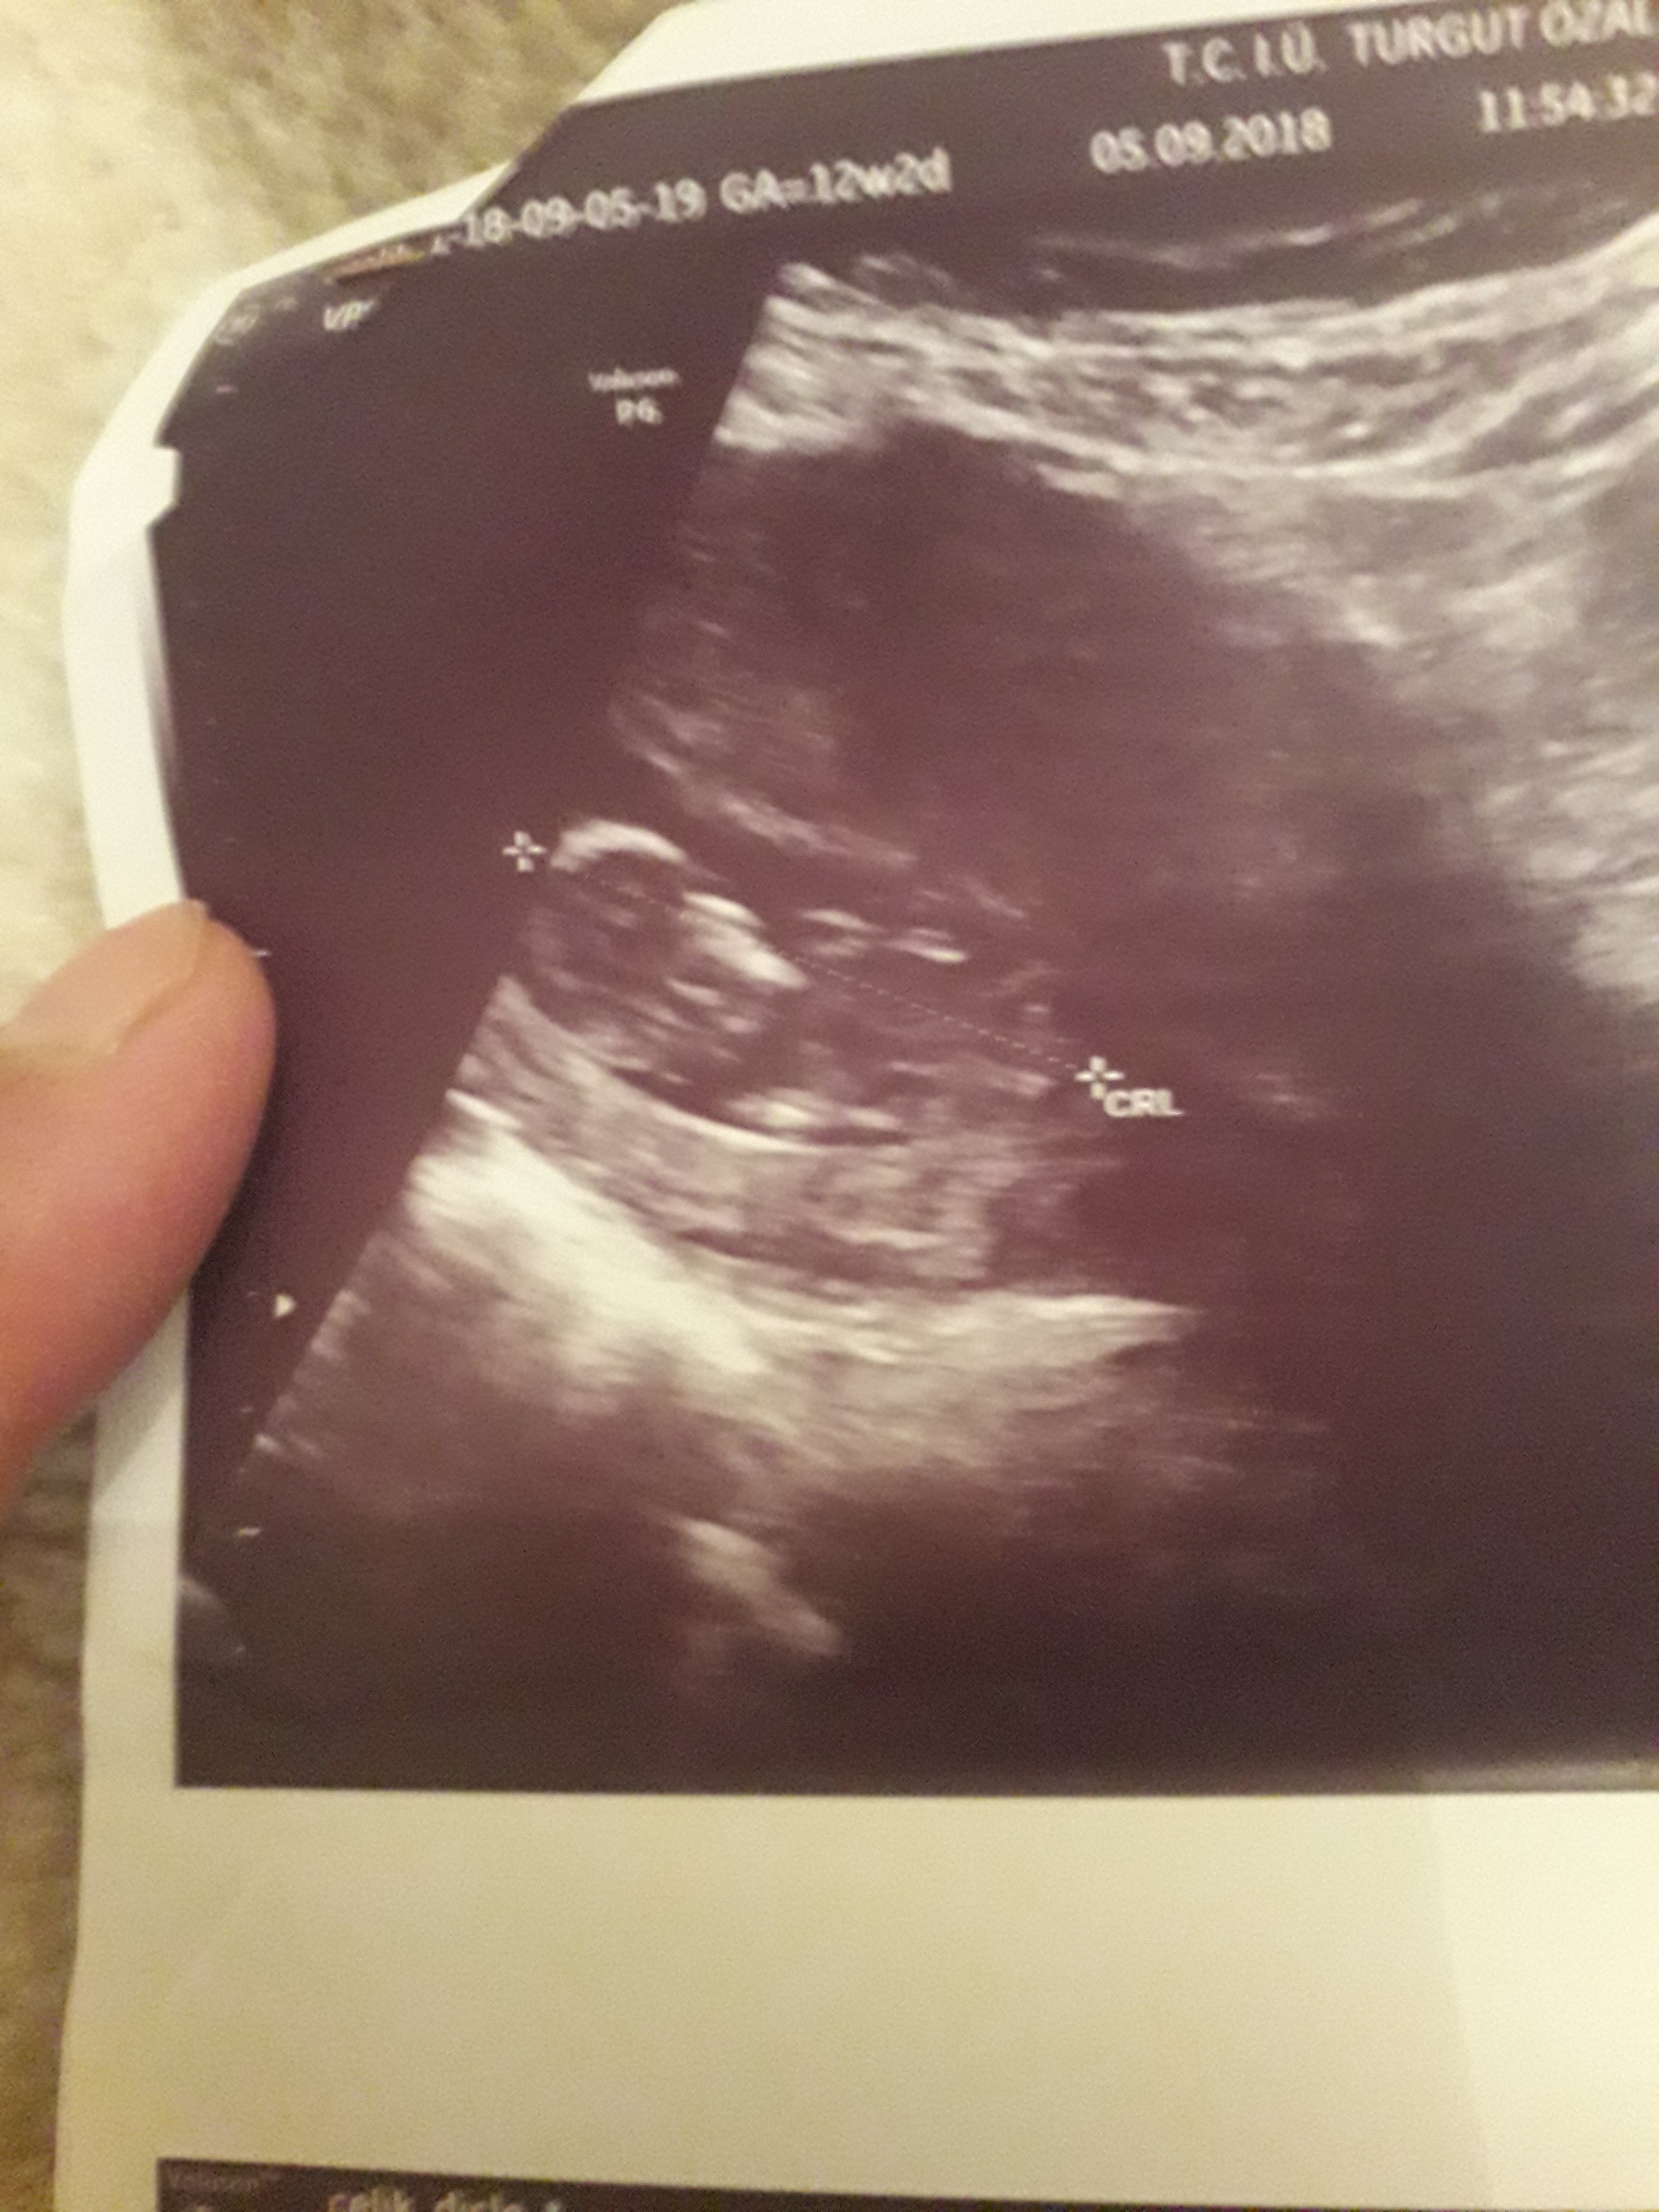

Banada yorum.yapin lutfen 12 haftaligiz

1,7 MB · Görüntüleme: 792

Nub teorsisi için cinsiyet tahmininde yorum isteyen arkadaşlar lütfen uyarımızı dikkate alın. Ultrason görüntüleri elinize ilk verildiği gibi net olmaz. Sık sık ışığa maruz kaldığı için görüntü kalitesi bozuluyor dolaysıyla bizlerde değerlendirme yapamıyoruz. Sizlere yorum yapabilmemiz için görüntü kalitesi aşağıdaki linkte yer alan görseller gibi olmalıdır. Ayrıca Bebeğin cinsiyeti net olarak 18-19-20. haftalarda belli olur..

Merhaba, yüklediğiniz görsellerde nub çıkıntısı anlaşılmıyor , dolaysıyla değerlendirme yapamıyoruz.. Görselin kalitesi aşağıdaki gibi olmaldır.. Sağlıklı gebelik süreci diliyorum.